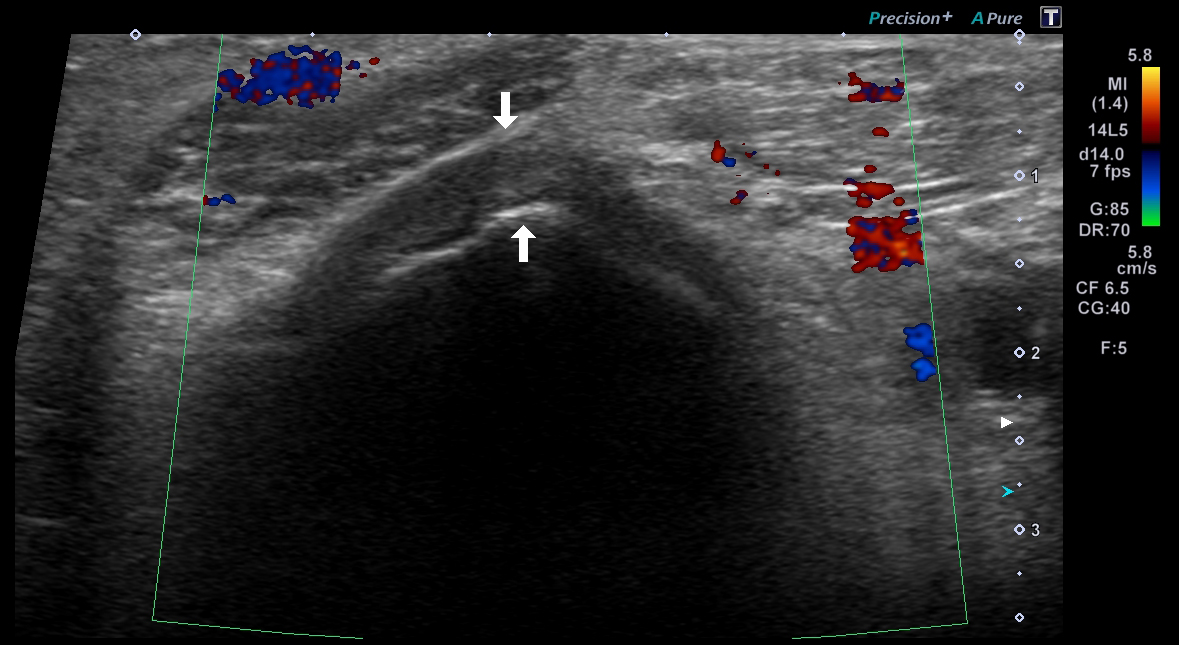

超音波(エコー) 診断画像

- 内頸動脈狭窄

- 静脈瘤